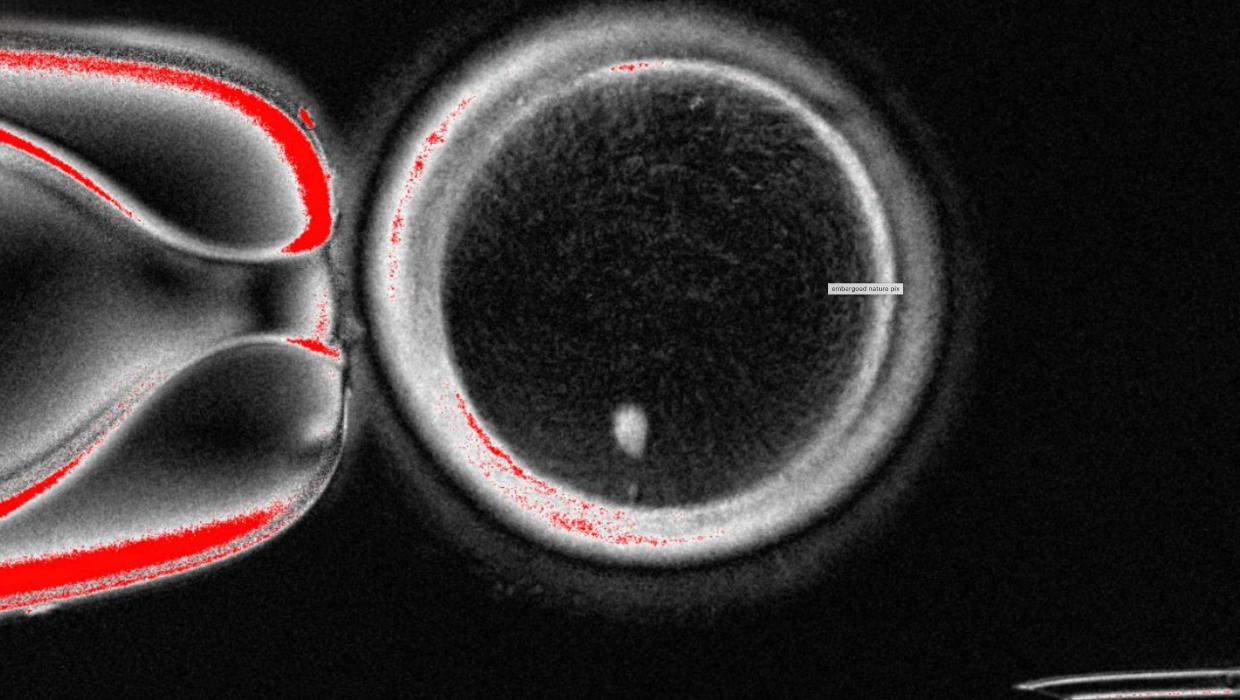

A team of researchers in the United States has successfully transformed human skin cells into fertilizable eggs, marking a significant advancement in reproductive science. This breakthrough, reported in early 2023, aims to pave the way for lab-grown eggs and sperm, potentially offering new options for individuals facing fertility challenges.

The research, conducted by a group at the University of California, Los Angeles (UCLA), involved reprogramming skin cells into induced pluripotent stem cells (iPSCs). These iPSCs were then guided to develop into oocytes, or immature eggs, that can be fertilized. This innovative approach could provide a vital alternative for people who are unable to conceive naturally or through traditional assisted reproductive technologies.